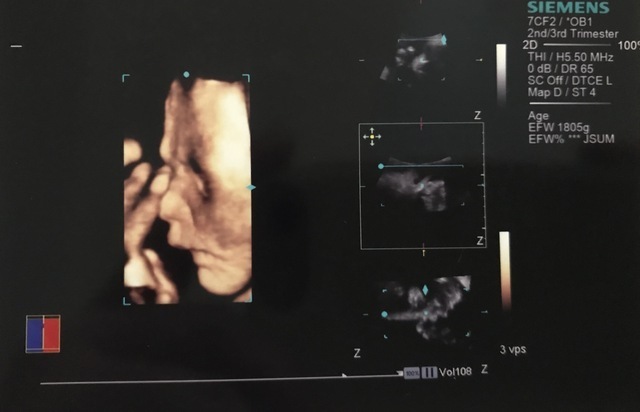

31週2日(31w2d・男の子)|花織 さん(23歳)

エコー写真撮影時のエピソード:

出産自体初めてのことで、 20代で子どもを産むことに色々不安を抱いていました。ですが、このエコーを見たとき、 初めて手がハッキリと見えて、小さいのにすごくしっかりしてることがわかりました。

母親としての実感が芽生えてはいましたが、改めて子どもを育てて行くという実感を感じることが出来ました。

このエコーのお陰ですごく元気づけられ、 産休に入るまでの間も仕事を続けることができ、 出産の一週間前まで働きました。 無理することはしないでできることをしながら 生まれてくる子どもの為に働けました。この時、 見えた手はすごく私に勇気をくれました。